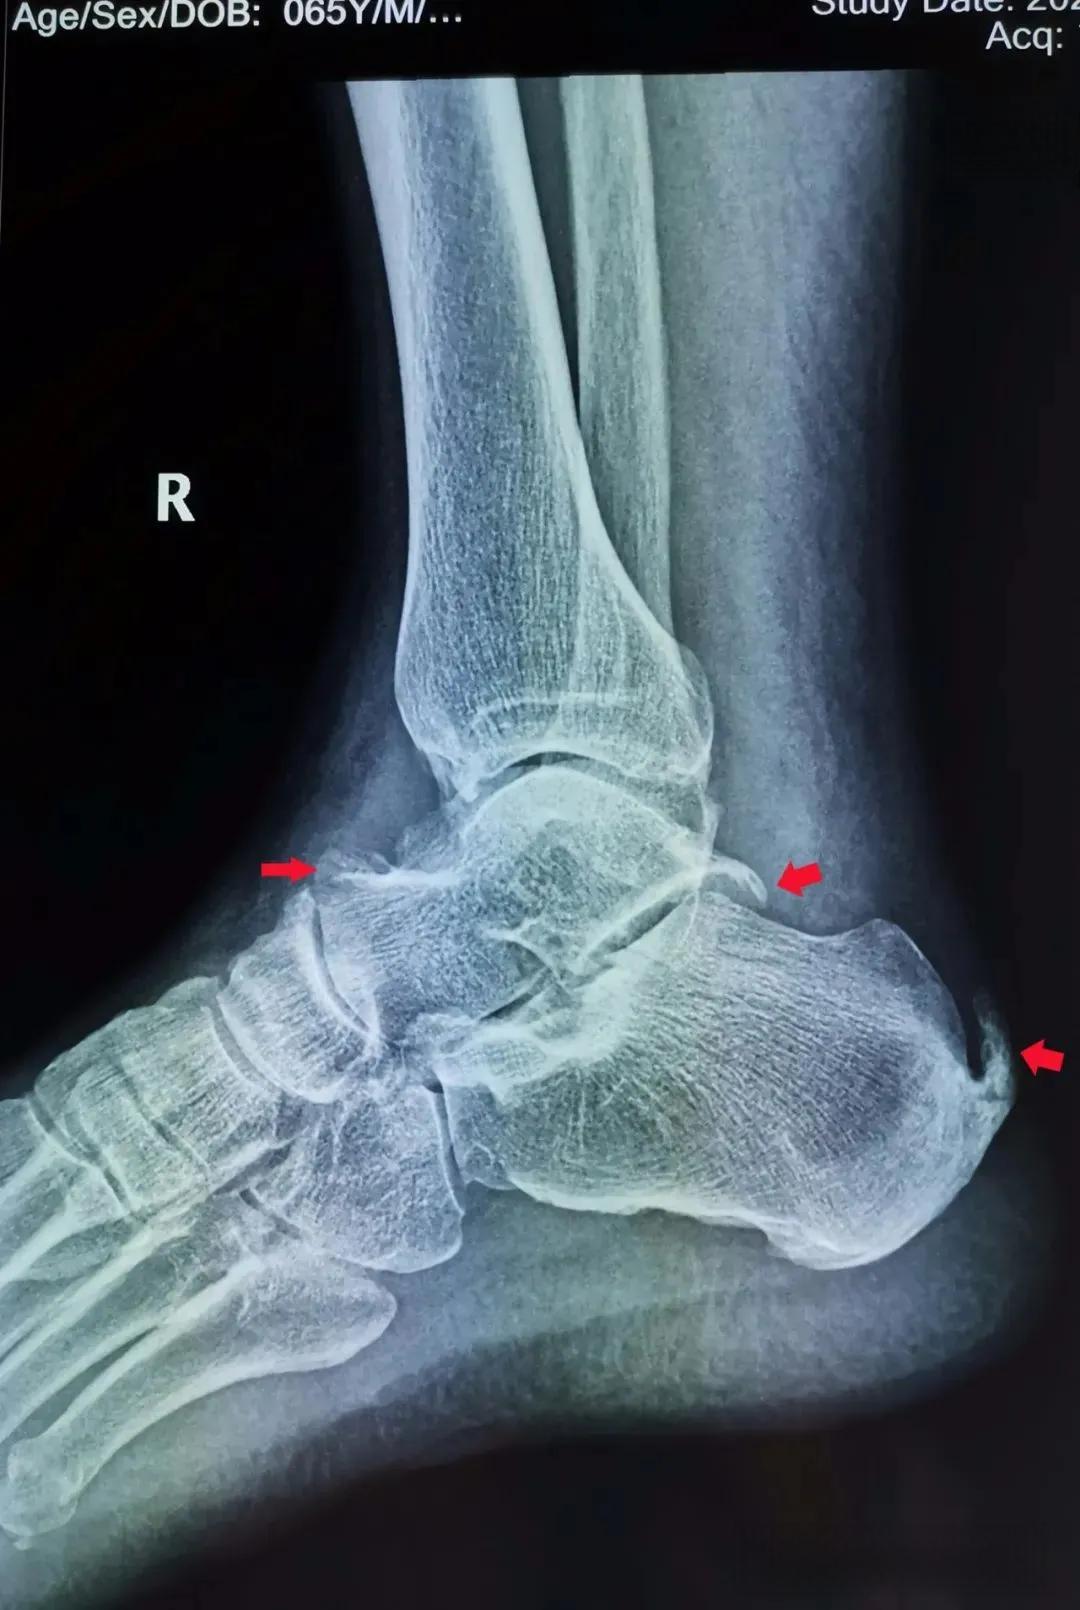

痛风的炎性刺激所致

痛风是一种常见的代谢性疾病,其特征是关节炎的急性发作,常表现为剧烈疼痛、红肿和发热。这种疾病的核心在于尿酸盐结晶在关节中的沉积,引发了一系列复杂的炎性反应。

炎症反应的直接结果是关节组织的红肿热痛。痛风患者常常在夜间突然发作,感到关节像被火烧一样疼痛。这是因为炎症介质不仅引起局部血管扩张,导致关节发红发热,还会刺激神经末梢,产生剧烈疼痛。同时,关节周围的组织也会因炎症而肿胀,限制关节的活动范围。

值得注意的是,痛风的发作往往具有自限性。在未经治疗的情况下,大多数急性发作会在7-14天内自行缓解。这是因为机体自身的抗炎机制逐渐发挥作用,炎症反应逐渐消退。然而,如果不加以控制,痛风可能会反复发作,甚至发展为慢性痛风性关节炎,导致关节损伤和功能障碍。